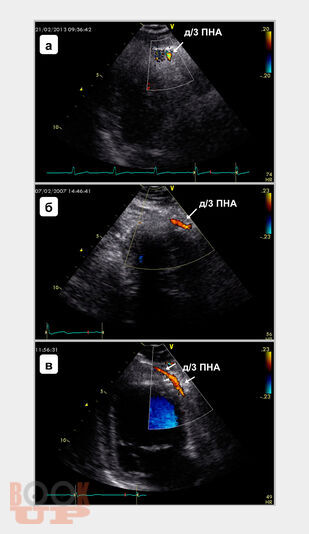

В монографии подробно изложены основные принципы трансторакального ультразвукового исследования магистральных коронарных артерий, включая методические и технические особенности визуализации, обсуждены параметры ламинарного, турбулентного и коллатерального коронарного кровотока, способы оценки и алгоритмы диагностики коронарных стенозов и окклюзий. Также представлены методика определения, способы расчета и критерии оценки резерва коронарного кровотока при трансторакальной допплерографии, показаны диагностическая и прогностическая роли показателя при выявлении гемодинамически значимых коронарных стенозов, окклюзий и определении лечебного эффекта интракоронарных интервенционных вмешательств. Книга рассчитана на кардиологов, врачей функциональной и ультразвуковой диагностики, эндоваскулярных хирургов, патофизиологов, студентов медицинских вузов.